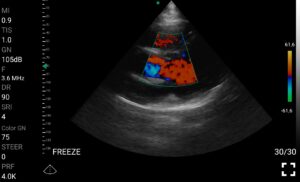

Παραδείγματα

Ολες οι παραπάνω απεικονιστικές εξετάσεις έχουν ληφθεί από φορητή συσκευή όπως: Apple Iphone, Tablet, Samsung Mobile Phones και διάφορες άλλες φορητές συσκευές.

• Doppler καρδιακών βαλβίδων: Βασική εκτίμηση στένωσης/ανεπάρκειας.

Παραδείγματα Video